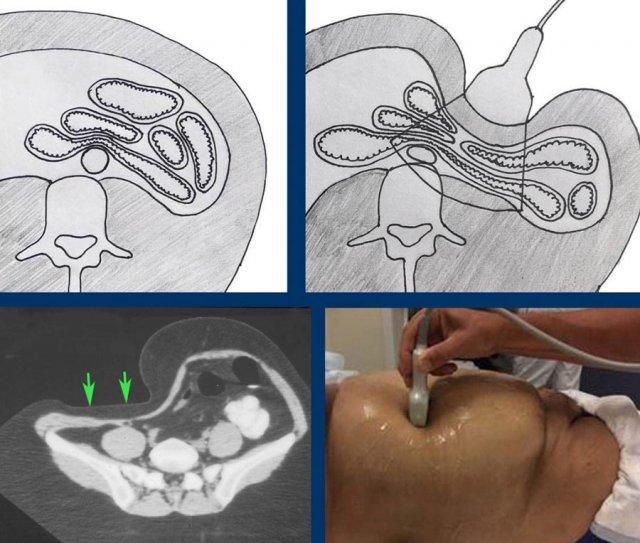

Hình ảnh CT cho thấy các mối tương quan giải phẫu trong ổ bụng thay đổi như thế nào khi ép có kiểm soát.

Trong quá trình ép, thành trước của ruột bị ép sát vào thành sau, loại bỏ tác động gây nhiễu của hơi và các thành phần khác trong lòng ruột.

Hình ảnh CT cắt dọc này cho thấy ruột thừa viêm nằm sau manh tràng (đầu mũi tên) với sỏi phân gây tắc nghẽn (mũi tên).

Bằng cách ép có kiểm soát bằng đầu dò siêu âm, manh tràng chứa hơi bị đẩy sang một bên và ruột thừa được hiển thị gần thành bụng (lưu ý thang đo cm).

Để hiển thị một cấu trúc hình ống (ví dụ: ruột thừa viêm) trên hai mặt phẳng vuông góc, điều cần thiết là đưa cấu trúc đó vào mặt cắt ngang ở trung tâm hình ảnh siêu âm.

Điều này cho phép giữ cấu trúc trong tầm nhìn trong khi xoay đầu dò 90 độ (nhấp vào hình).

Nhẹ nhàng “lắc” đầu dò trong khi xoay giúp giữ cấu trúc hình ống nhỏ trong tầm quan sát.